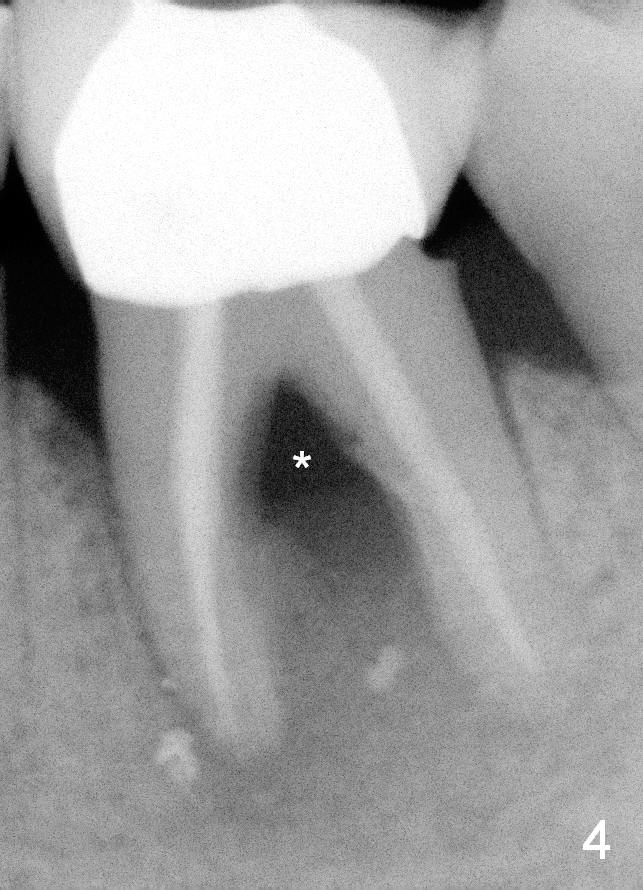

A 59-year-old lady has history of periodontal disease and bruxism.  The tooth #19 has pulpitis after unsuccessful DO composite (Fig.1 *) and requires root canal therapy (Fig.2).  Six months later, a fistula is found to communicate with the furca (Fig.3 *: gutta percha).  Less than 3 years, the furca enlarges with symptoms of infection (Fig.4 *).  She works out of state. The Principle of No Implant, No Extraction is adhered.  Since she is of short statue, the bone height is relatively limited.  A 6x14 mm tissue-level implant is appropriate (Fig.5, one piece).  Sensor 1 may be proper for her small mouth.  When the bottom of the socket is large and close to the Inferior Alveolar Nerve, can an immediate implant be placed?